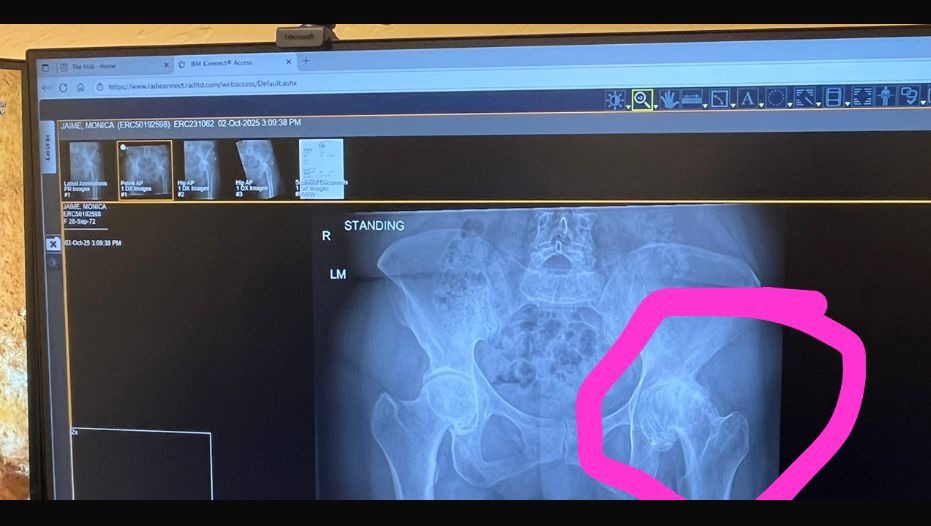

But unfortunately, she is in need of emergency hip surgery. She needs this done as soon as possible as she is at risk of infection if she does not get the surgery soon. She is someone who loves to dance, and if it is not done soon, she will end up in a wheelchair for the rest of her life. She needs all the help she can get. She is aware the holidays are approaching, but Monica and her family would be truly grateful for any donations.

Pero, lamentablemente, necesita una cirugía de cadera de emergencia. Necesita que esto se haga lo antes posible, ya que corre riesgo de infección si no recibe la cirugía pronto. A ella le encanta bailar, y si no se realiza la operación, podría terminar en una silla de ruedas por el resto de su vida. Necesita toda la ayuda que pueda recibir. Sabemos que se acercan los días festivos, pero Mónica y su familia estarían verdaderamente agradecidos por cualquier donación.